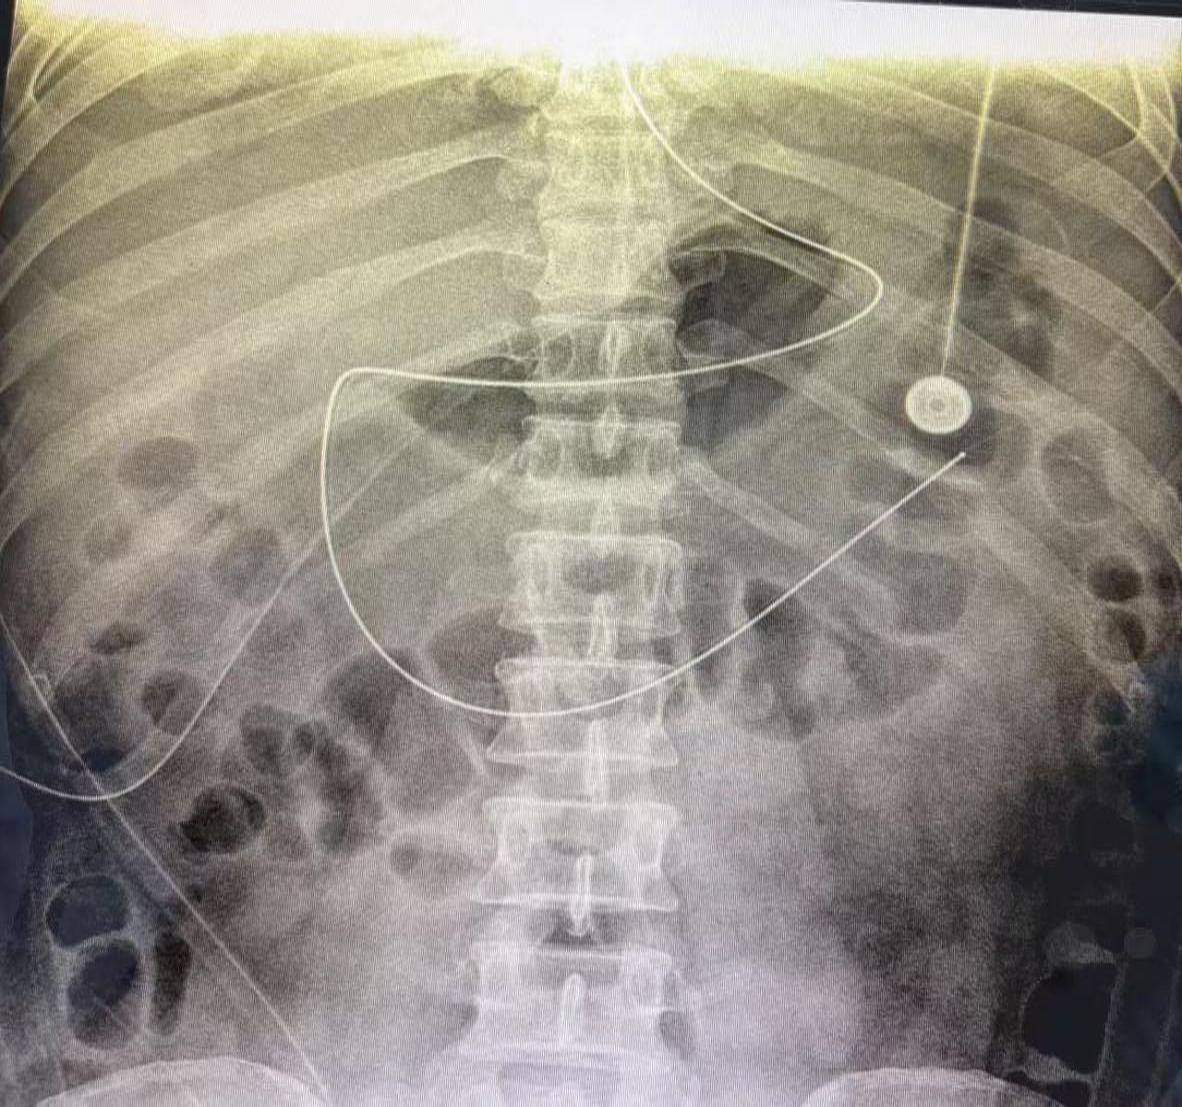

在充分告知家属并取得同意后,由重症医学科医护团队主导操作。凭借扎实的专业技能,在无任何辅助设备引导下,通过娴熟的手法将鼻肠管经鼻腔送入幽门,最终成功置入十二指肠并进入空肠。经床旁数字化X光(DR)验证,鼻肠管末端呈现清晰的"大C"形影像,确认置管位置精准无误,整个过程患者耐受良好,未出现并发症。

“鼻肠管盲插技术通过绕过胃部直达空肠,有效避免了胰液过度分泌风险,为患者开辟了安全的营养通道。”光山县人民医院重症医学科护师郑丽萍介绍,该技术具有操作便捷、创伤小、并发症少等优势,尤其适用于重症胰腺炎、胃肠功能障碍等需要早期肠内营养支持的患者。此次成功实施,不仅缩短了患者禁食时间,更为后续康复治疗奠定了坚实基础。